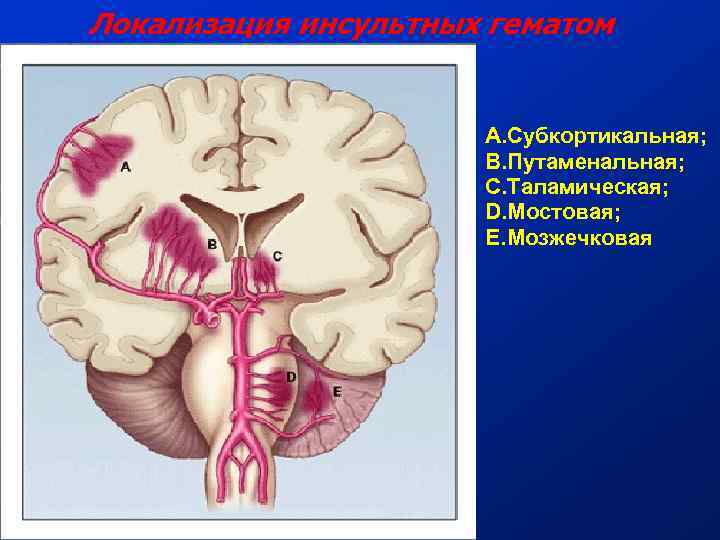

Иллюстрации и пояснения: гиподенсивный очаг на КТ головного мозга